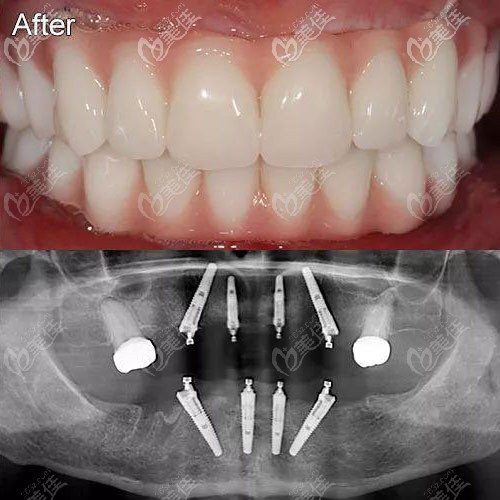

即刻拔牙后做半口瑞士士卓曼钛锆亲水种植牙,花了8.8万

图片尺寸656x477